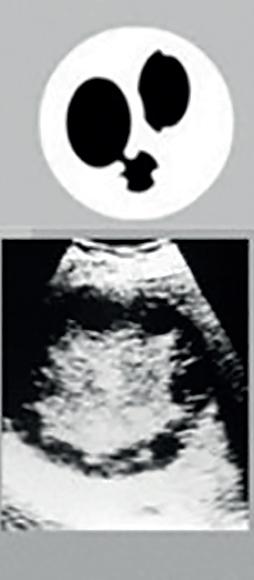

The Positive Effect of Water Immersion on Labor Progress Assessed by Intrapartum Ultrasound Examination

Pozytywny wpływ zastosowania immersji wodnej na postęp porodu oceniany metodą ultrasonografii śródporodowej